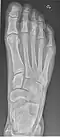

- Foot / Toes - Dorsoplantar, Oblique and Lateral.[19]

-

Normal right foot by dorsoplantar projection -

Oblique projection -

Lateral projection